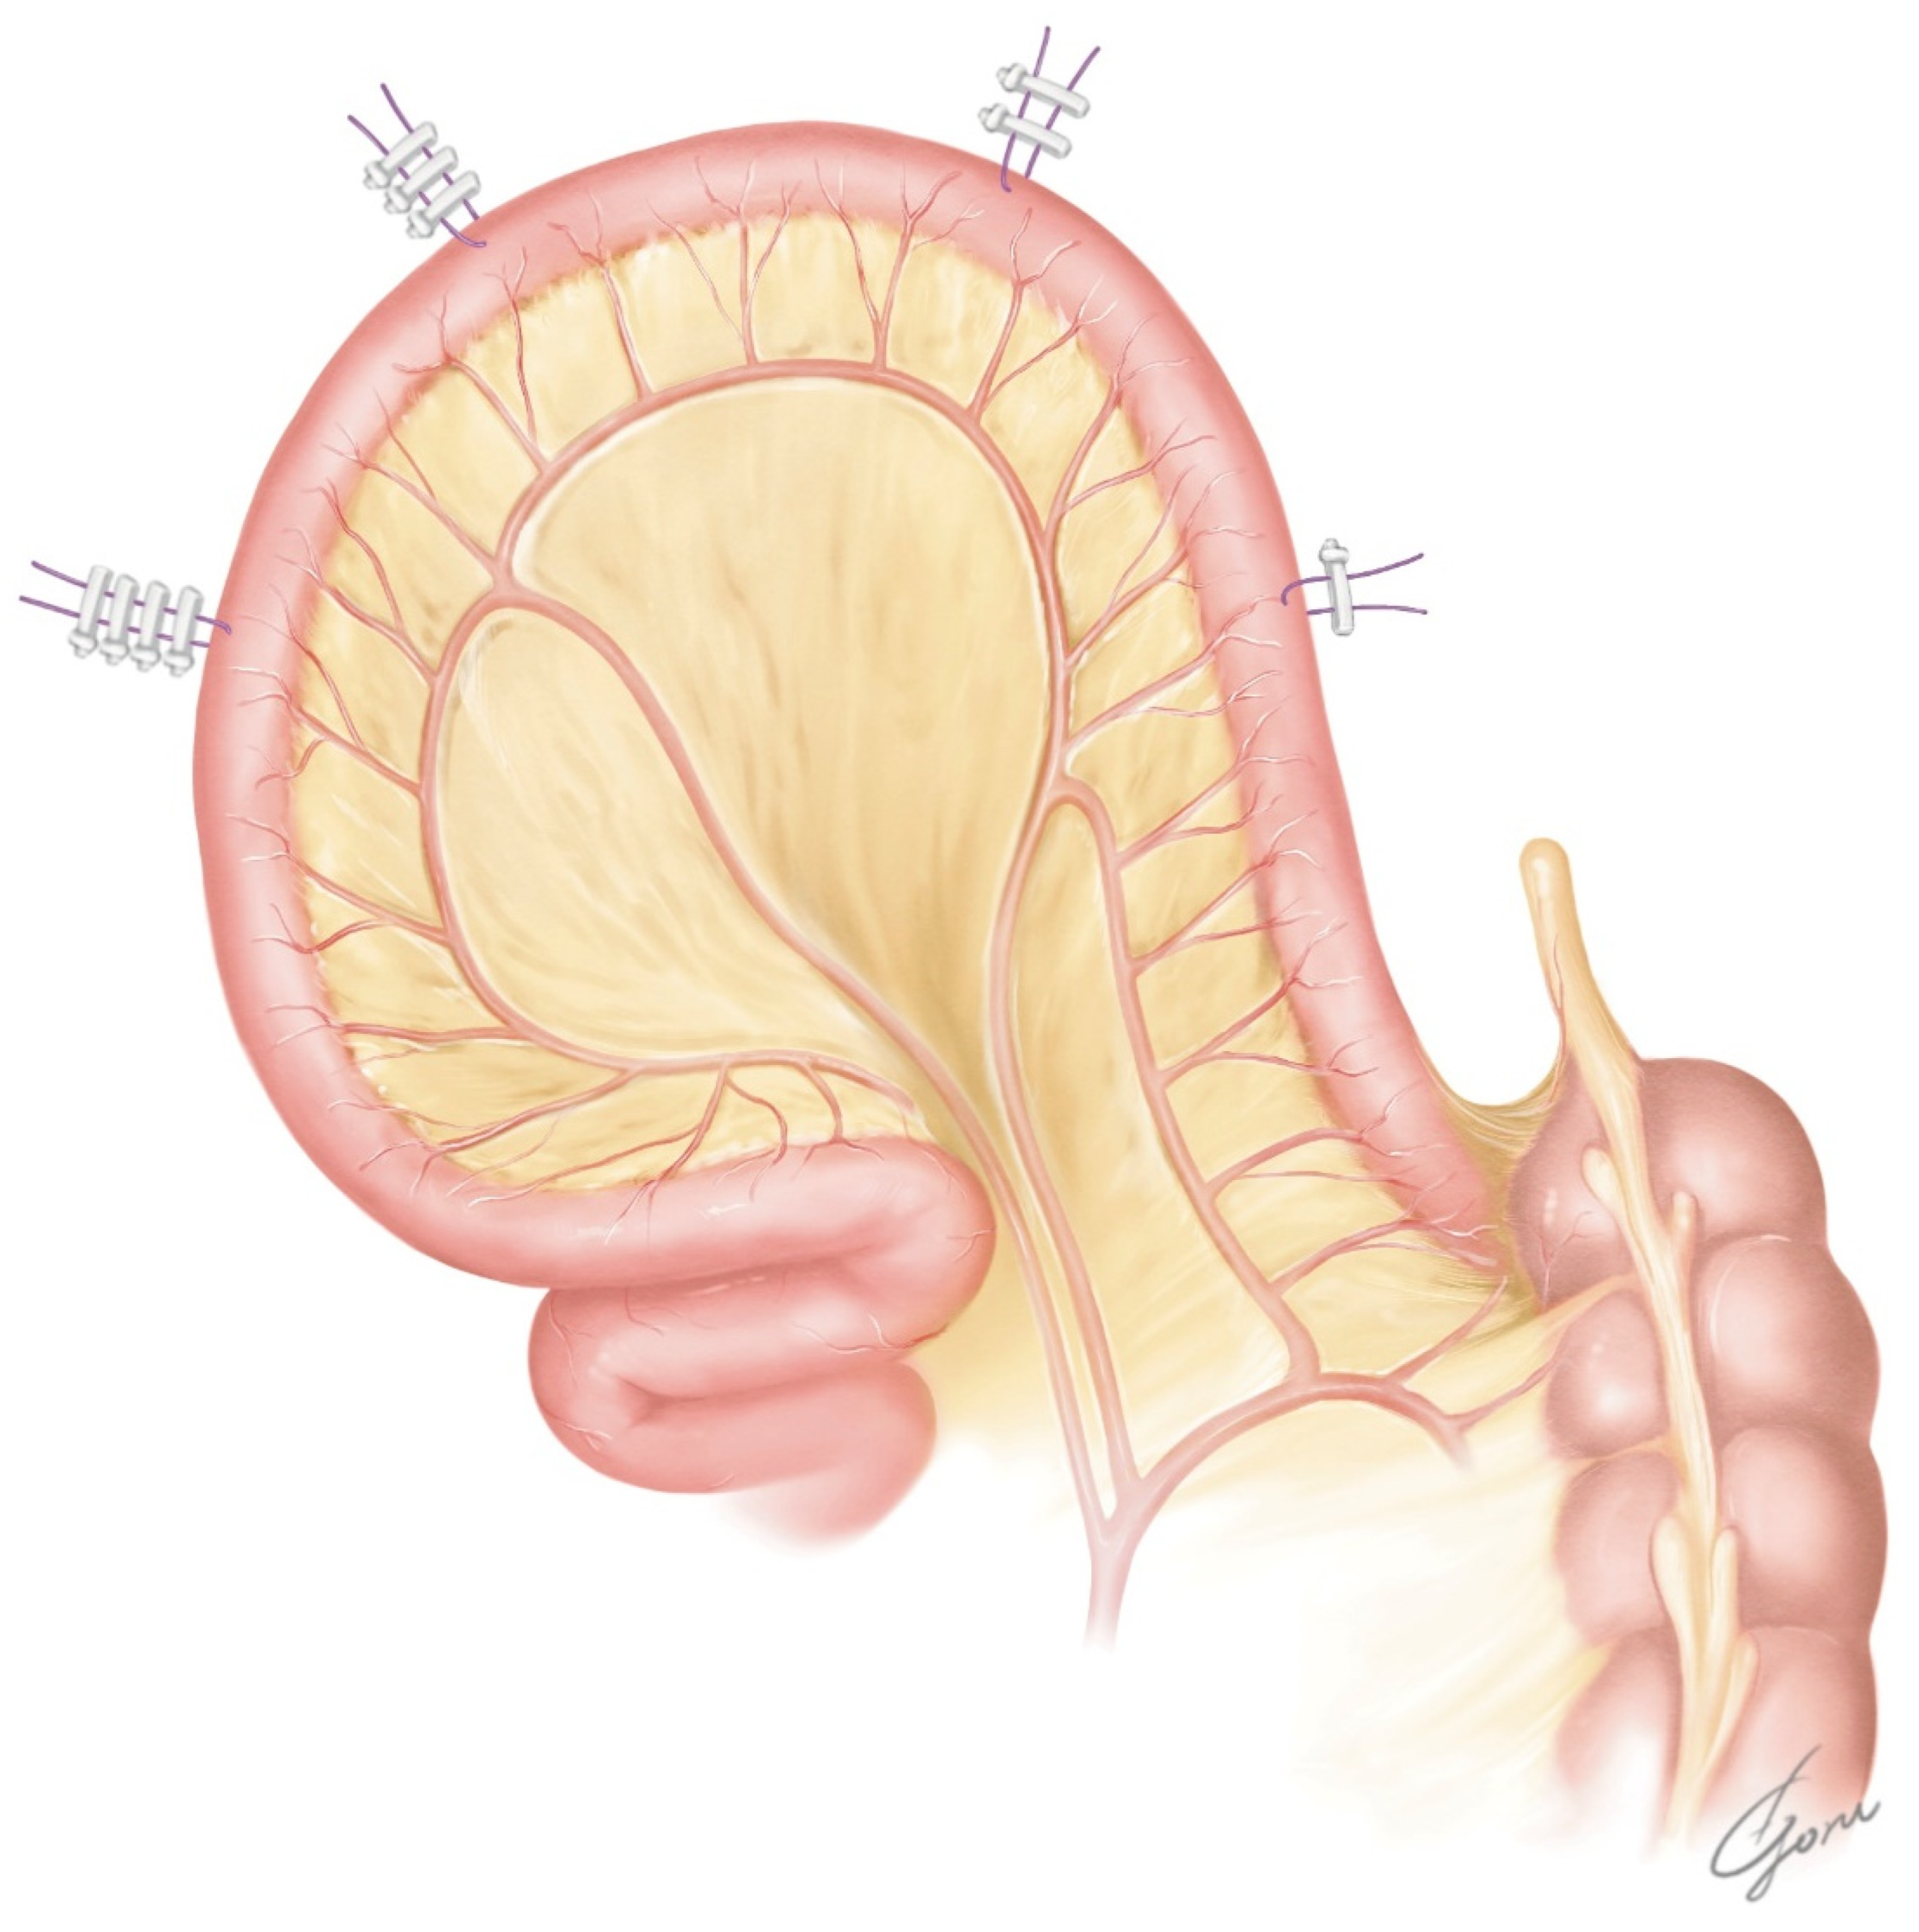

After undocking the robot, an infraumbilical midline incision of approximately 7 cm was placed, and the bladder specimen was removed. An Alexis wound retractor (Medical Leaders, Tokyo, Japan) was placed and the ileum was dissected extracorporeally according to the markings. Then, a side-to-side ileoileal anastomosis was performed using a 60 mm EndoGIA stapler (Covidien, Medtronic, Tokyo, Japan). Approximately 45 cm of ileum was then detubularized, leaving 10 cm of the afferent limb. The ileum near the urethra–ileal anastomosis was incised slightly closer to the mesentery. We placed two supporting sutures with a clip on the ileum near the urethra–ileal anastomosis for traction. Figure 2 shows the design of our posterior plate, which is ovular. It has a reverse spiral shape opposite to that of the original VIP method to allow it to move the afferent limb forward. Additionally, the posterior wall of the original VIP was rotated 90 degrees counterclockwise to allow the NB to be folded from the side to the center. When the formation of the posterior plate of the NB was completed, it was checked again to determine whether the posterior plate could be moved to the level of the pubic bone. If mobilization of the posterior plate was still difficult at this point, additional dissection of the mesentery or a relaxing incision of the mesentery was considered. With the 6Fr ureteral stent passing through the afferent limb, the posterior plate was returned to the intracorporeal. The Alexis wound retractor was capped.

Figure 2.

The design of our posterior plate using the modified VIP method. Two supporting sutures were placed on the ileum near the urethra–ileal anastomosis.